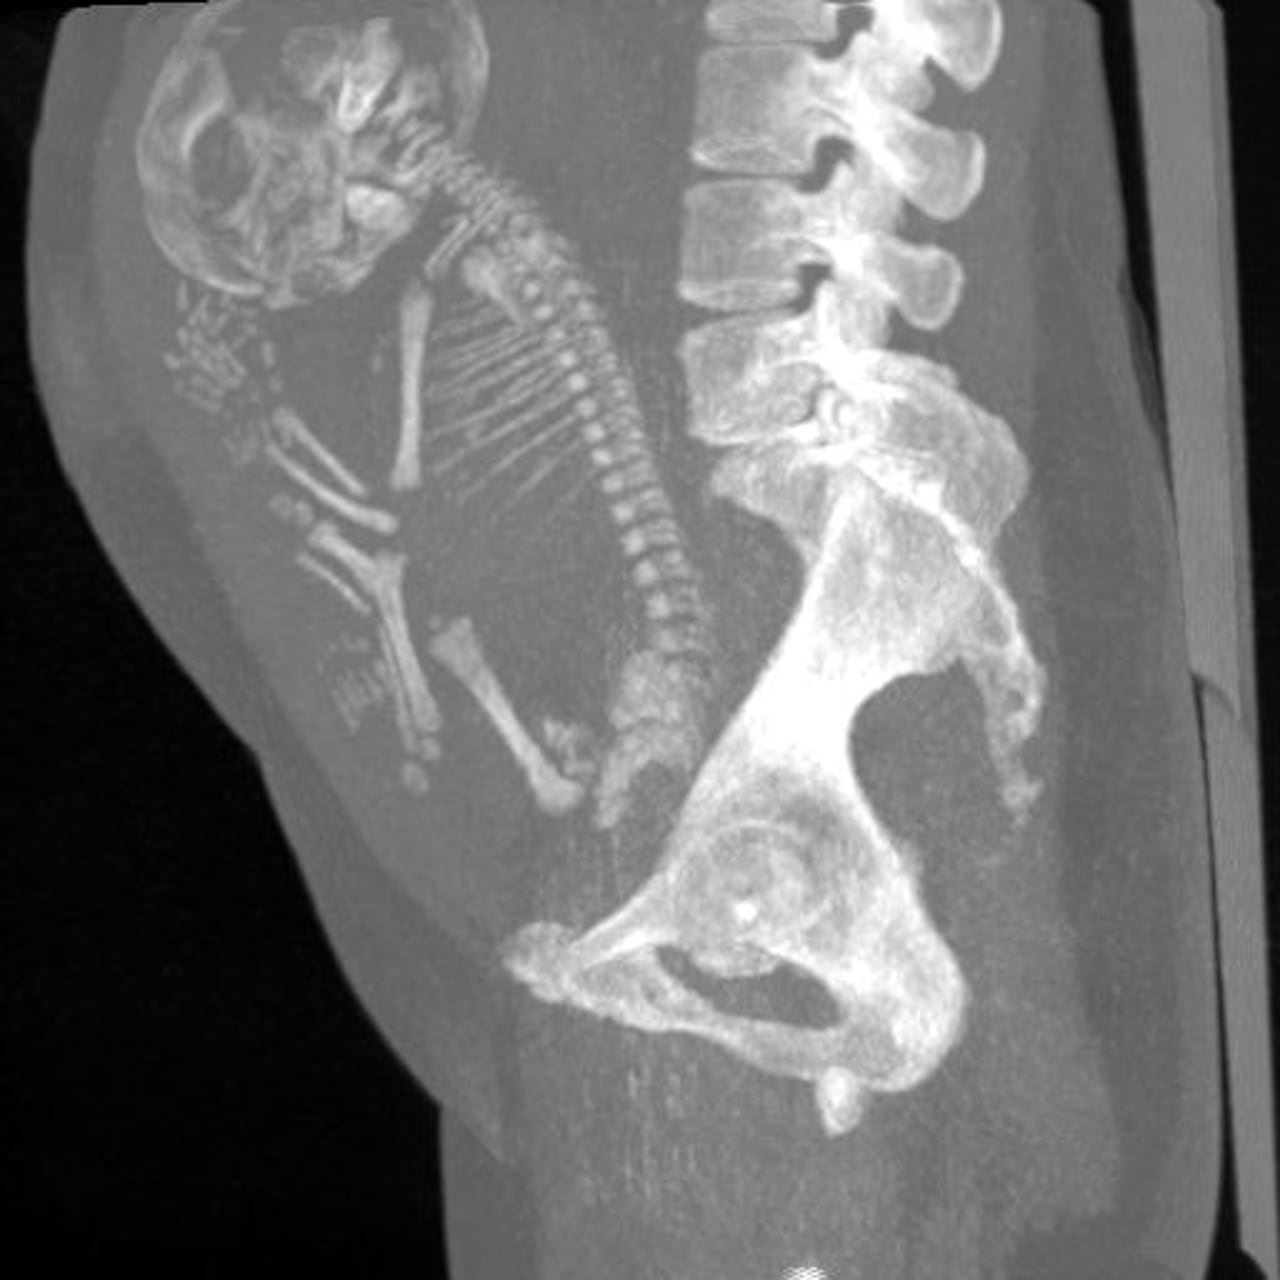

Impactante: una mujer de 84 años fue al médico por un dolor abdominal y resultó teniendo un feto momificado en su vientre

A una anciana que se quejaba de dolor de vientre se le descubrió que tenía un feto momificado en su interior, un hecho que llamó la atención de los médicos en México, donde se presentó el caso, específicamente en el estado de Durango.

La mujer, de quien no se conoce su identidad, habría estado embarazada sin darse cuenta durante 40 años, lo que generó que el feto dentro de su vientre se momificara; fue entonces cuando un dolor de estómago la obligó a asistir al médico, donde los expertos en salud confirmaron la presencia del feto.

En cuanto a la explicación científica de este inusual hecho, los médicos creen que el feto se calcificó, en un raro evento llamado lithopaedion, que es extraordinariamente raro, en el que el exterior del cuerpo del feto se calcifica como parte del intento del cuerpo de la madre de protegerse.

Es así como parte de una reacción a un cuerpo extraño para proteger a la madre del tejido muerto y de contraer una infección. Los médicos calculan que el bebé murió y fue momificado en la semana 40 del embarazo después de no desarrollarse normalmente, según el Daily Star.

Según Public Med Central, este inusual caso médico se puede describir como un embarazo ectópico abdominal en el que el feto muere, pero no puede ser reabsorbido por el cuerpo de la madre. El feto muerto queda retenido en la cavidad abdominal, formando una capa de calcio a su alrededor.

El litopedion se ha descrito en mujeres con edades comprendidas entre 23 y 100 años, siendo dos tercios de ellas mayores de 40 años. El período de retención del feto fue de 4 a 60 años. En este caso, se desconoce el período de retención exacto, pero es razonable pensar que podría ser al menos 40 años.